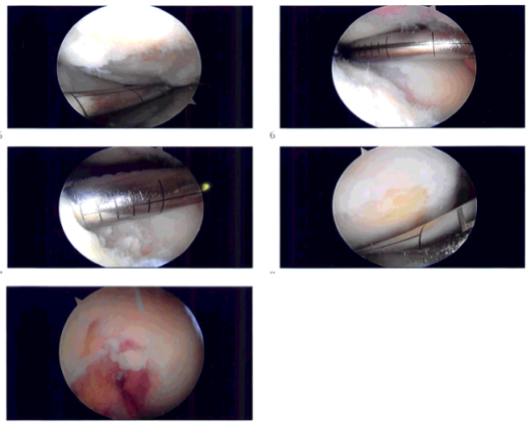

Intraoperative images

The tourniquet was elevated to 250 mmHg. After exsanguination an incision was made. The lateral portal anesthesia was given. A medial anterior portal incision was made with the use of a spinal needle. There was arthritis along the medial femoral condyle and medial tibial plateau. The meniscus was intact.

There was a Grade IV defect of the medial femoral condyle which was debrided with the use of curette and debrided and abrasion chondroplasty was performed with the use of a curette. The defect was measured and was 1.5 cm by 1.5 cm.

Examination revealed an intact ACL. Examination noted lateral tibial tendon patellofemoral compartment showed intact cartilage. Examination of the patellofemoral compartment showed intact cartilage over the patella but there was Grade III to Grade IV osteochondral lesion of the trochlea.

Debridement of this lesion was performed to stable margins. The defect was measured to be 1.5 cm x 1 cm. All of the measurements were taken. All of the pictures were taken and saved. The knee was drained. Closure was done with 3-0 nylon.